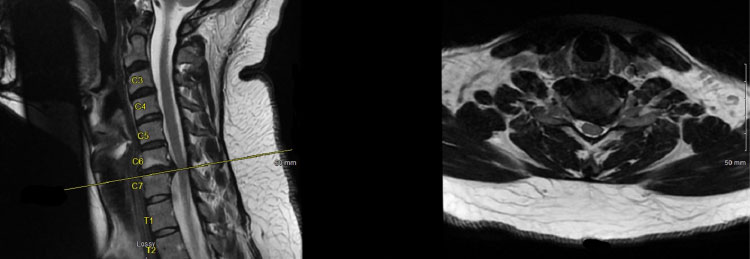

Below are the pre-operative MRI cervical spine images showing a left-sided C6/C7 herniated disc with pressure on the existing left C7 nerve root.